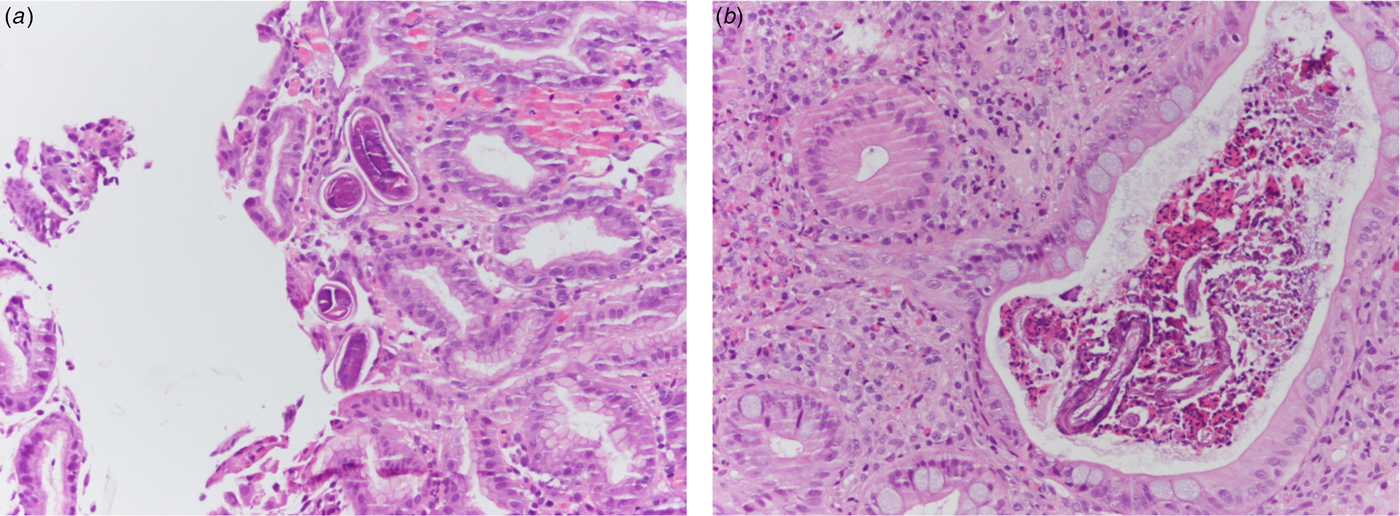

As shown in Figure 4, most tests were prescribed in the first semester of the activities (August 2017–February 2018): accounting for 74.4% of tests performed in the whole study period. Two patients out of 42 (4.8%) were found positive to serological screening (one autochthonous patient and one immigrant), but an additional autochthonous patient was diagnosed in the same study period by gastric biopsy. Two of the positive patients were born in San Marino, aged >80 years and had no history of travels outside San Marino/Italy (‘autochthonous cases’). The other positive patient was a 31-year-old man born in Nigeria and arrived in Europe (Italy first, then San Marino) in 2003. Median values of eosinophil count was 860 (IQR 351–1834) for positive patients, and 232 (IQR 113–449) for negative patients, as shown in Figure 5. Of note, the two autochthonous cases had moderate-high eosinophilia (from 860 to 1834 cells/μl upon diagnosis), while the patient from Nigeria had an eosinophil count of 351 cells/μl. All patients with positive serology presented compatible symptoms, in particular all patients reported abdominal pain and/or diarrhoea. The Nigerian patient had an obstruction of the bowel. One of them also reported weight loss and hyporexia. None of them was immunocompromised. The two patients from San Marino received treatment with ivermectin, with good clinical response. The African patient left San Marino before receiving treatment.

Fig. 5. Median and IQR values of eosinophil count in patients with positive and negative serological result.